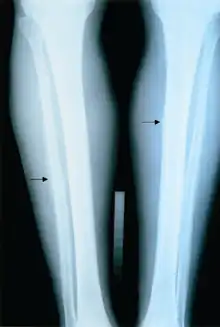

The diagnosis for Skeletal fibrosis can be done via its radiographic presentation[9]